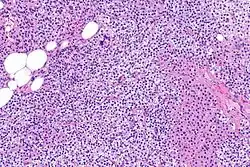

Hyperparathyroidism, in general, is caused by either tumorous growth in one or more parathyroid glands or a prolonged decrease in blood calcium levels or hypocalcaemia which in turn stimulates the production of parathyroid hormone release from the parathyroid gland.[10][11] The parathyroid gland is located beside the thyroid gland in the neck, below and in front of the larynx and above the trachea. It is composed of four glands in total that monitor blood calcium levels via the calcium sensing receptors, a g-coupled protein receptor.[12] The parathyroid glands main role is calcium homeostasis.[13][12] Histologically, these glands are composed of chief cells and oxyphil cells with the chief cell primarily responsible for the storing and release of parathyroid hormone. These cells are arranged in a pseudo-follicular pattern similar to the thyroid follicles. Keratin staining is used to image the parathyroid hormone granules.[9][14]

Primary hyperplasia of the parathyroid gland, results from both hypocalcaemia and increased phosphate levels by decreasing expression of calcium sensing receptors and vitamin D receptors at the parathyroid gland.[8][4] These decreases in receptor expression lead to hyperfunctioning of the parathyroid. Hyperfunction of the parathyroid gland is thought to exacerbate primary hyperplasia which evolves further to a secondary more aggressive hyperplasia. Histologically, these hyperplasic glands can be either diffuse or nodular.[24] Primary hyperplasia, usually resulting in diffuse polyclonal growth is manly related to reversible secondary hyperparathyroidism. Secondary hyperplasia of the parathyroid gland is more often a nodular, monoclonal growth that sustains secondary hyperparathyroidism and is the catalyst in the progression to tertiary hyperparathyroidism. Nodular hyperplastic glands in tertiary hyperparathyroidism are distinctly larger in both absolute size and weight up to 20-40-fold increases have been reported.[25][26][24]

Parathyroid glands are normally composed of chief cells, adipocytes and scattered oxyphil cells.[27][14] Chief cells are thought to be responsible for the production, storage and secretion of parathyroid hormone. These cells appear light and dark with a prominent Golgi body and endoplasmic reticulum. In electron micrographs, secretory vesicles can be seen in and around the Golgi and at the cell membrane. These cells also contain prominent cytoplasmic adipose.[27][14] Upon onset of hyperplasia these cells are described as having a nodular pattern with enlargement of protein synthesis machinery such as the endoplasmic reticulum and Golgi. Increased secretory vesicles are seen and decreased intercellular fat is characteristic.[27][24] Oxyphil cells also appear hyperplasic however, these cells are much less prominent.